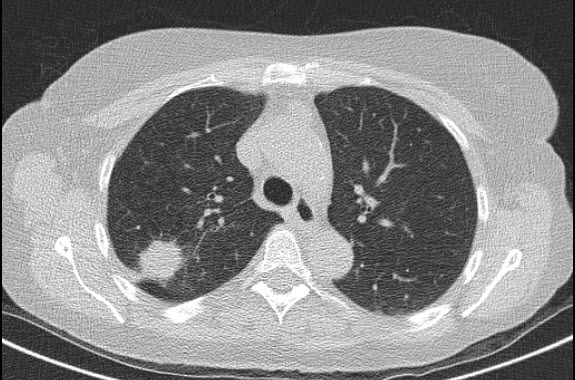

image.png

###### Ryc. [D](http://radiologyassociatesimaging.com/did-you-know-a-patient-education-article-regarding-lung-cancer-cancer-screening/) - fragment badania TK klatki piersiowej, który w oknie płucnym uwidacznia masę patologiczną w górnym płacie płuca prawego. ###### W Polsce odbyły się pilotażowe programy przesiewowe zorganizowane przez nieliczne ośrodki akademickie. Badaniu uczestniczyło 50 000 osób z grupy ryzyka, wśród których wykryto około 500 przypadków raka. Przedstawiciele rządu polskiego nie planują w najbliższym czasie wprowadzanie NDTK jako rutynowego darmowego badania. Istnieje możliwość, że po opublikowaniu wyników randomizowanego badania **NELSON** prowadzonego w Holandii, stanowisko polskiej grupy ekspertów ulegnie wzmocnieniu.